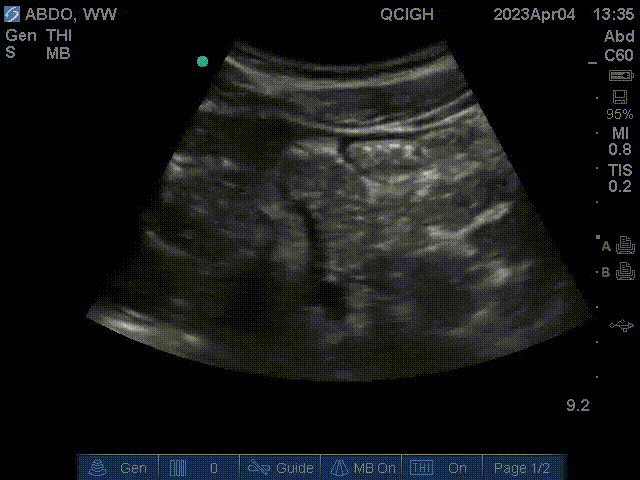

Aortic scan – bifurcation

The aortic scan may be used to detect an abdominal aortic aneurysm (AAA). This scan requires visulatization of the aorta starting from the external landmark of the xiphoid process to the aortic bifurcation into the common iliac vessels. A vessel size of ≥ 3cm at any point constitutes AAA.

The IVC collapses easily with pressure (shown on image left, anatomic right). The aorta remains round with pressure (shown on image right, anatomic left). The vessels lie anterior to the spine, which casts a shadow posteriorly.